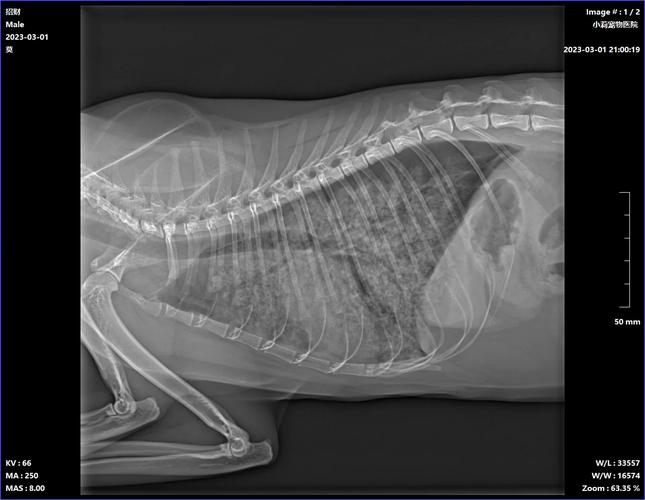

新生幼猫出现肺炎的症状通常分为以下几个方面:第猫咪表现鼻腔分泌物增加。第猫咪会出现精神食欲下降,可能同时伴有体温增高。第肺部感染严重,可能会表现出猫咪呼吸急促。如果猫咪出现上述症状时,建议及时带到宠物医院进行血常规、胸部影像学的检查。

〖叁〗、猫咪感染肺炎是常见的疾病,主要症状包括呼吸急促、咳嗽、打喷嚏、体温升高等。如果你的猫咪出现了这些症状,应该及时带它去兽医那里进行检查和治疗。兽医在诊断猫咪是否感染了肺炎时,一般会做一些血液检查、X光检查以及痰液检测等。如果确诊猫咪感染了肺炎,那么治疗方式一般包括抗生素、消炎药和止咳药等。